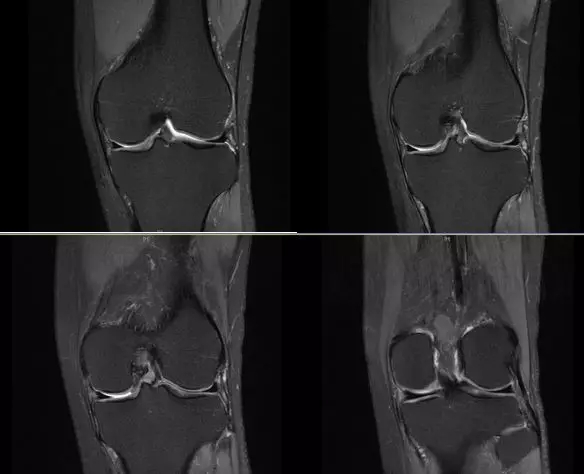

正常的膝关节

韧带结构:形态,张力,质地,连续性

半月板:完整性,形态,质地